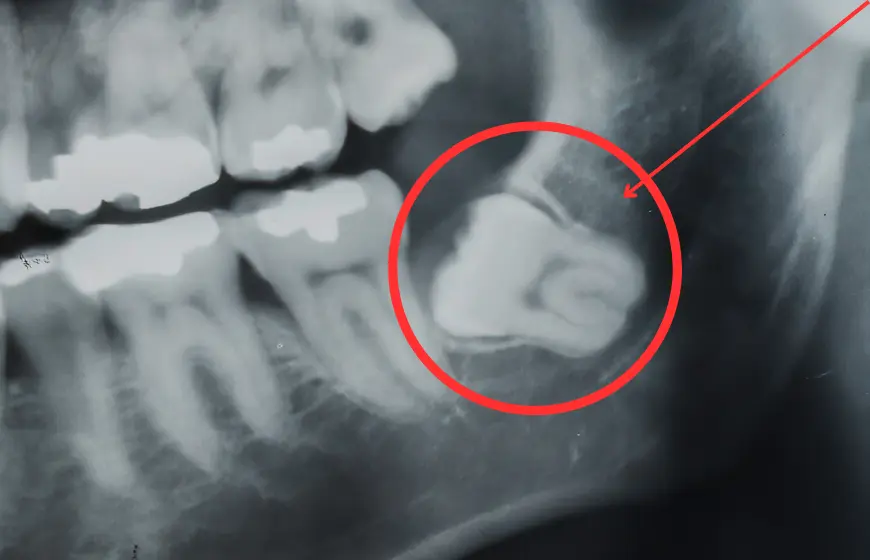

Zęby zatrzymane i planowanie chirurgiczne – CBCT jako mapa przed odsłonięciem lub ekstrakcją

Zatrzymany ząb sieczny, kieł lub premolar to problem obecny na panoramie – widać, że ząb nie wyrżnął się, widać zarys jego korony i korzenia w projekcji. Nie widać jednak, po której stronie blaszki kostnej się znajduje – podniebiennie czy wargowo; jak daleko od korzeni sąsiednich zębów jego korzeń przebiega; czy blaszka kostna nad koroną zatrzymanego zęba jest zwarta, czy już rozrzedzona od ucisku. Na tych danych oparty jest plan zabiegu: kierunek dostępu chirurgicznego, ryzyko dla sąsiednich korzeni, konieczność usunięcia lub możliwość trakcji ortodontycznej.

Tomografia CBCT zębów dostarcza tych danych w pełnej trójwymiarowości. Lekarz – stomatolog lub ortodonta – widzi zatrzymany ząb w modelu przestrzennym: koronę z dokładnością do milimetra, relację do korzeni sąsiednich zębów, grubość kości nad koroną i po każdej ze stron. Decyzja o chirurgicznym usuwaniu lub ortodontycznym odsłonięciu i trakcji zapada z danymi, które wykluczają najważniejsze źródła powikłań śródoperacyjnych.

Dodatkowym wskazaniem jest diagnostyka ósemek w sąsiedztwie korzeni drugich trzonowców dolnych. Resorpcja dystalnego korzenia siódemki przez zatrzymaną ósemkę to powikłanie typowo skryte, odkrywane czasem dopiero gdy siódemka jest nie do uratowania. CBCT wykonane z wyprzedzeniem pokazuje, jak bliskie jest sąsiedztwo i czy bieżące ułożenie ósemki stwarza ryzyko – zanim dojdzie do nieodwracalnego uszkodzenia korzenia.

Na tej samej zasadzie CBCT stosowane jest przy diagnostyce zatrzymanych kłów dziecięcych, zębów nadliczbowych (mezjodensu) wciśniętych między korzenie siekaczy i anomalii liczby zębów. Każdy przypadek, gdzie trójwymiarowa lokalizacja zęba wpływa na plan zabiegu chirurgicznego lub ortodontycznego, jest potencjalnym wskazaniem do badania.

- Orientacja przestrzenna zatrzymanego zęba – strona dostępu chirurgicznego (wargowa/podniebienna/językowa) widoczna bezpośrednio; eliminuje najczęstsze zaskoczenie śródoperacyjne

- Relacja do korzeni sąsiednich – odległość i kontakt z korzeniami sąsiednich zębów mierzalne w milimetrach; ryzyko uszkodzenia identyfikowane przed nacięciem

- Resorpcja korzenia siódemki przez ósemkę – typ i zasięg uszkodzenia widoczny na CBCT zanim jest klinicznie lub radiologicznie wykrywalny na projekcji 2D; decyzja o ekstrakcji ósemki z wyprzedzeniem

- Grubość kości nad koroną zatrzymanego zęba – grubość blaszki kostnej zmierzona przed zabiegiem; lekarz planuje technikę i zasięg preparacji przed pierwszym cięciem